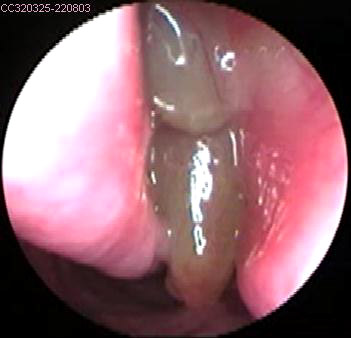

JFC Cuerpo extraño en laringe. hueso de pavo.